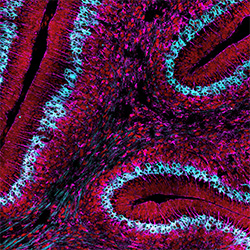

Mapping the Developing Mind: Spatial Transcriptomics Reveals the Early Origin of Bergmann Glia

The Millen Lab solves a 50-year mystery in cerebellar development. Published in PNAS, this research uses spatial transcriptomics to redefine the timeline of Bergmann glia and correct long-standing inaccuracies in brain science.

Mapping the Emergence of Neurons in the Developing Brain

Seattle Children’s neuroscience researchers mapped and described the very earliest emergence of neurons in the developing human cerebellum.

Pinpointing the Origin of Deadly Brain Tumors

In two papers published in Nature, Dr. Kathleen Millen and her team are the first to identify the cells that give rise to the most aggressive forms of medulloblastoma.